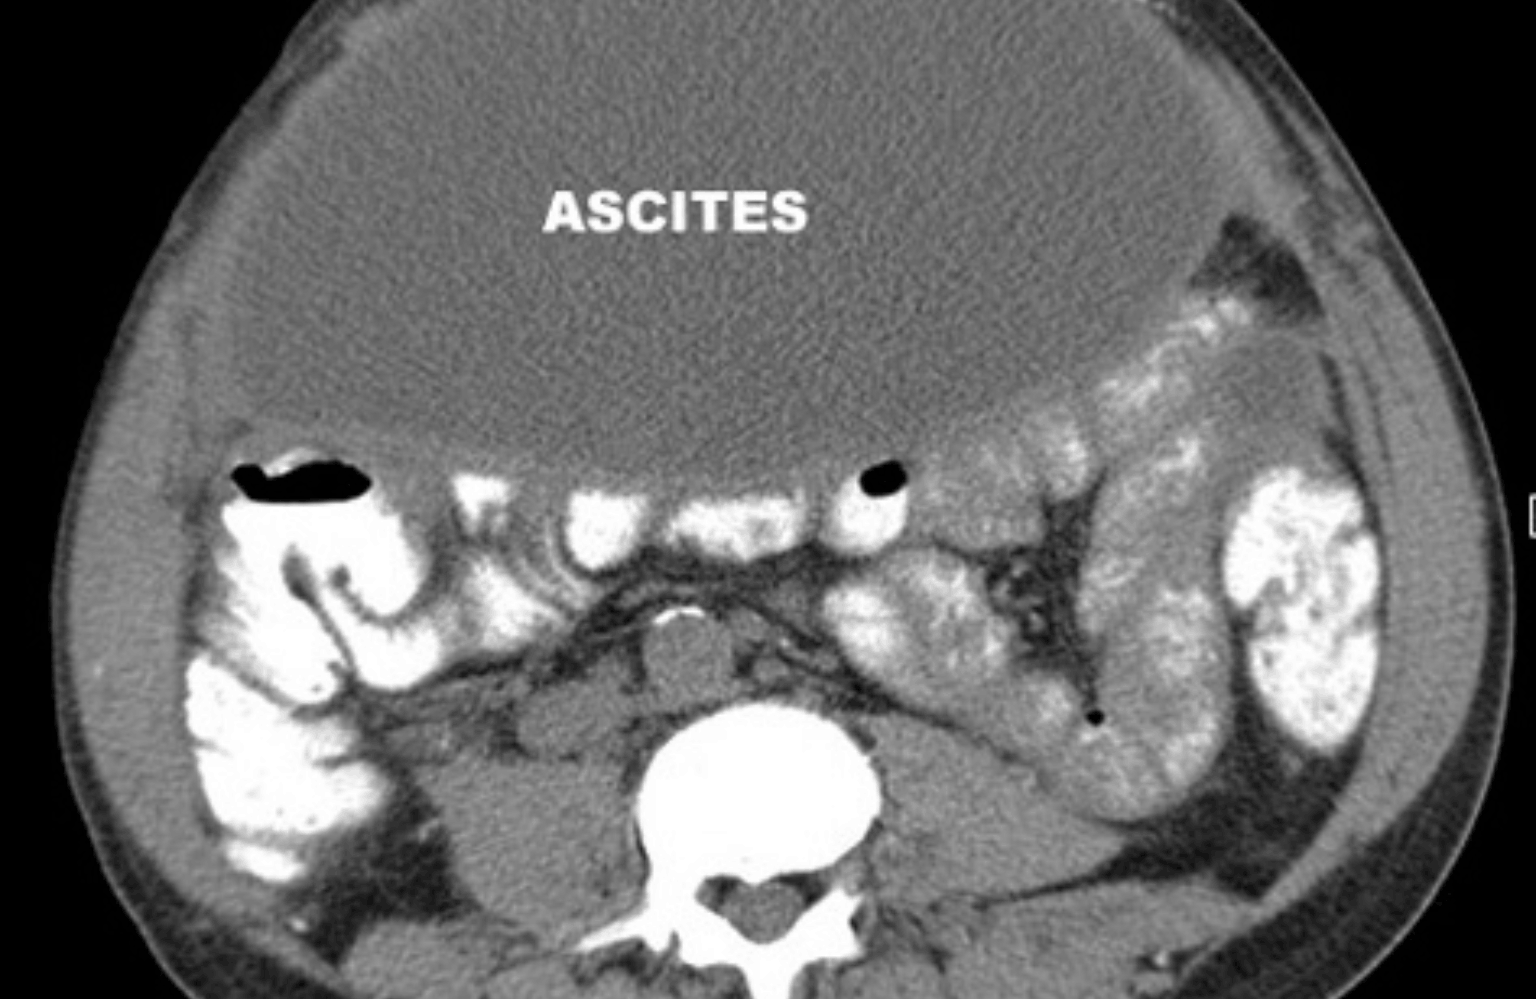

Ascites

Ascites is the abnormal accumulation of fluid in the abdominal (peritoneal) cavity. In Ayurveda, this condition is classified under the major disease category of Udararoga (Diseases of the Abdomen). There are eight types of abdominal diseases described in classical texts, with (Water-Belly) or being the specific term for the stage where fills the . It is considered a severe condition arising from chronic and the aggravation of all three Doshas.

Ayurvedic Definition:Udararoga refers to a generalized distension or enlargement of the abdomen. When this enlargement is specifically caused by the accumulation of water (Jala or Udaka) due to the blockage of sweat and water channels, it is defined as Jalodara. It represents a state of severe Agnimandya (loss of digestive fire) and Malasanchaya (accumulation of waste).